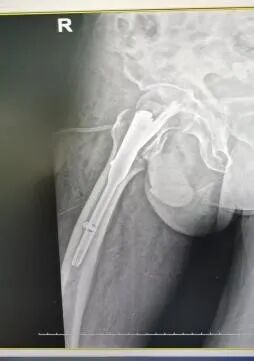

手术治疗:股骨转子间骨折闭合复位髓内钉内固定术。

股骨转子间骨折的手术治疗方法首选内固定手术,适用于大多数老年髋部骨折患者,骨科(创伤中心)熟练开展此类手术,具有创伤小,出血少,手术时间短(手术时间在30-60分钟),曾成功为104岁老人手术!做到了用微创解决骨折问题,术后第二天患者就可以下地做早期康复训练,有效地避免了卧床并发症,大大提高了病人的生活质量。

图片图片